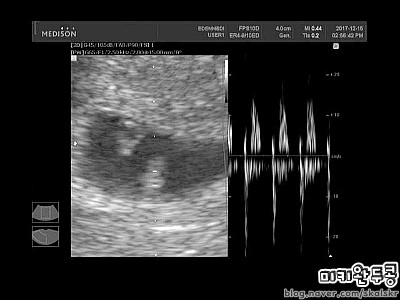

2017.12.15 헬롱이 심장소리 들은날_♥

2017.12.15 헬롱이 심장소리 들은날_ 첫 임신이라 걱정도 많이 되고 작은것 하나에도 가슴이 철렁거려서 소...